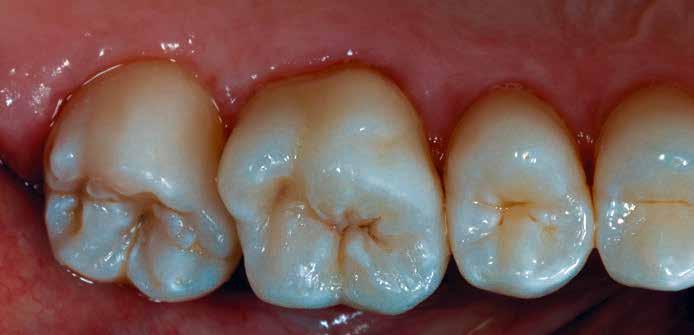

4. ábra: A durva finírozás után a restauráció pereme sima és anatómiailag is megfelelő.

6. ábra: I. osztályú restaurációk az első moláris és a második premoláris fogakban. A széleken felesleges kompozit figyelhető meg (piros nyilak jelölik).

12. ábra: A premoláris fogak preoperatív állapota.

13. ábra: A premoláris fogak postoperatív fotója.